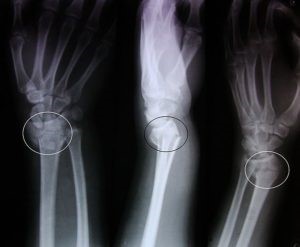

Лучевые методы диагностики являются «золотым стандартом» в диагностике переломов. Чаще всего в рутинной практике используется рентгенография конечности в двух проекциях.

Рентгеновский снимок покажет не только наличие перелома, но и его характер, наличие отломков, вид смещения и др. Эти данные играют ключевую роль в выборе лечебной тактики.

Иногда для диагностики сложных травм травматологи используют метод компьютерной томографии.